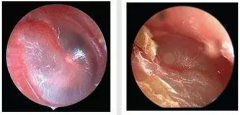

胆脂瘤型中耳乳突炎必须做手术吗 治疗案例

患者自幼双耳廓畸形,与人交谈困难。2年前出现左耳流黄色脓性分泌物并反复发作,分泌物有异味。伴有耳痛,呈持续性胀痛。半月前左耳后皮肤红肿,瘘口处有脓液。近一个月来患者自觉右耳听力比以前有下降。... [详情] 文章日期 :17-07-05